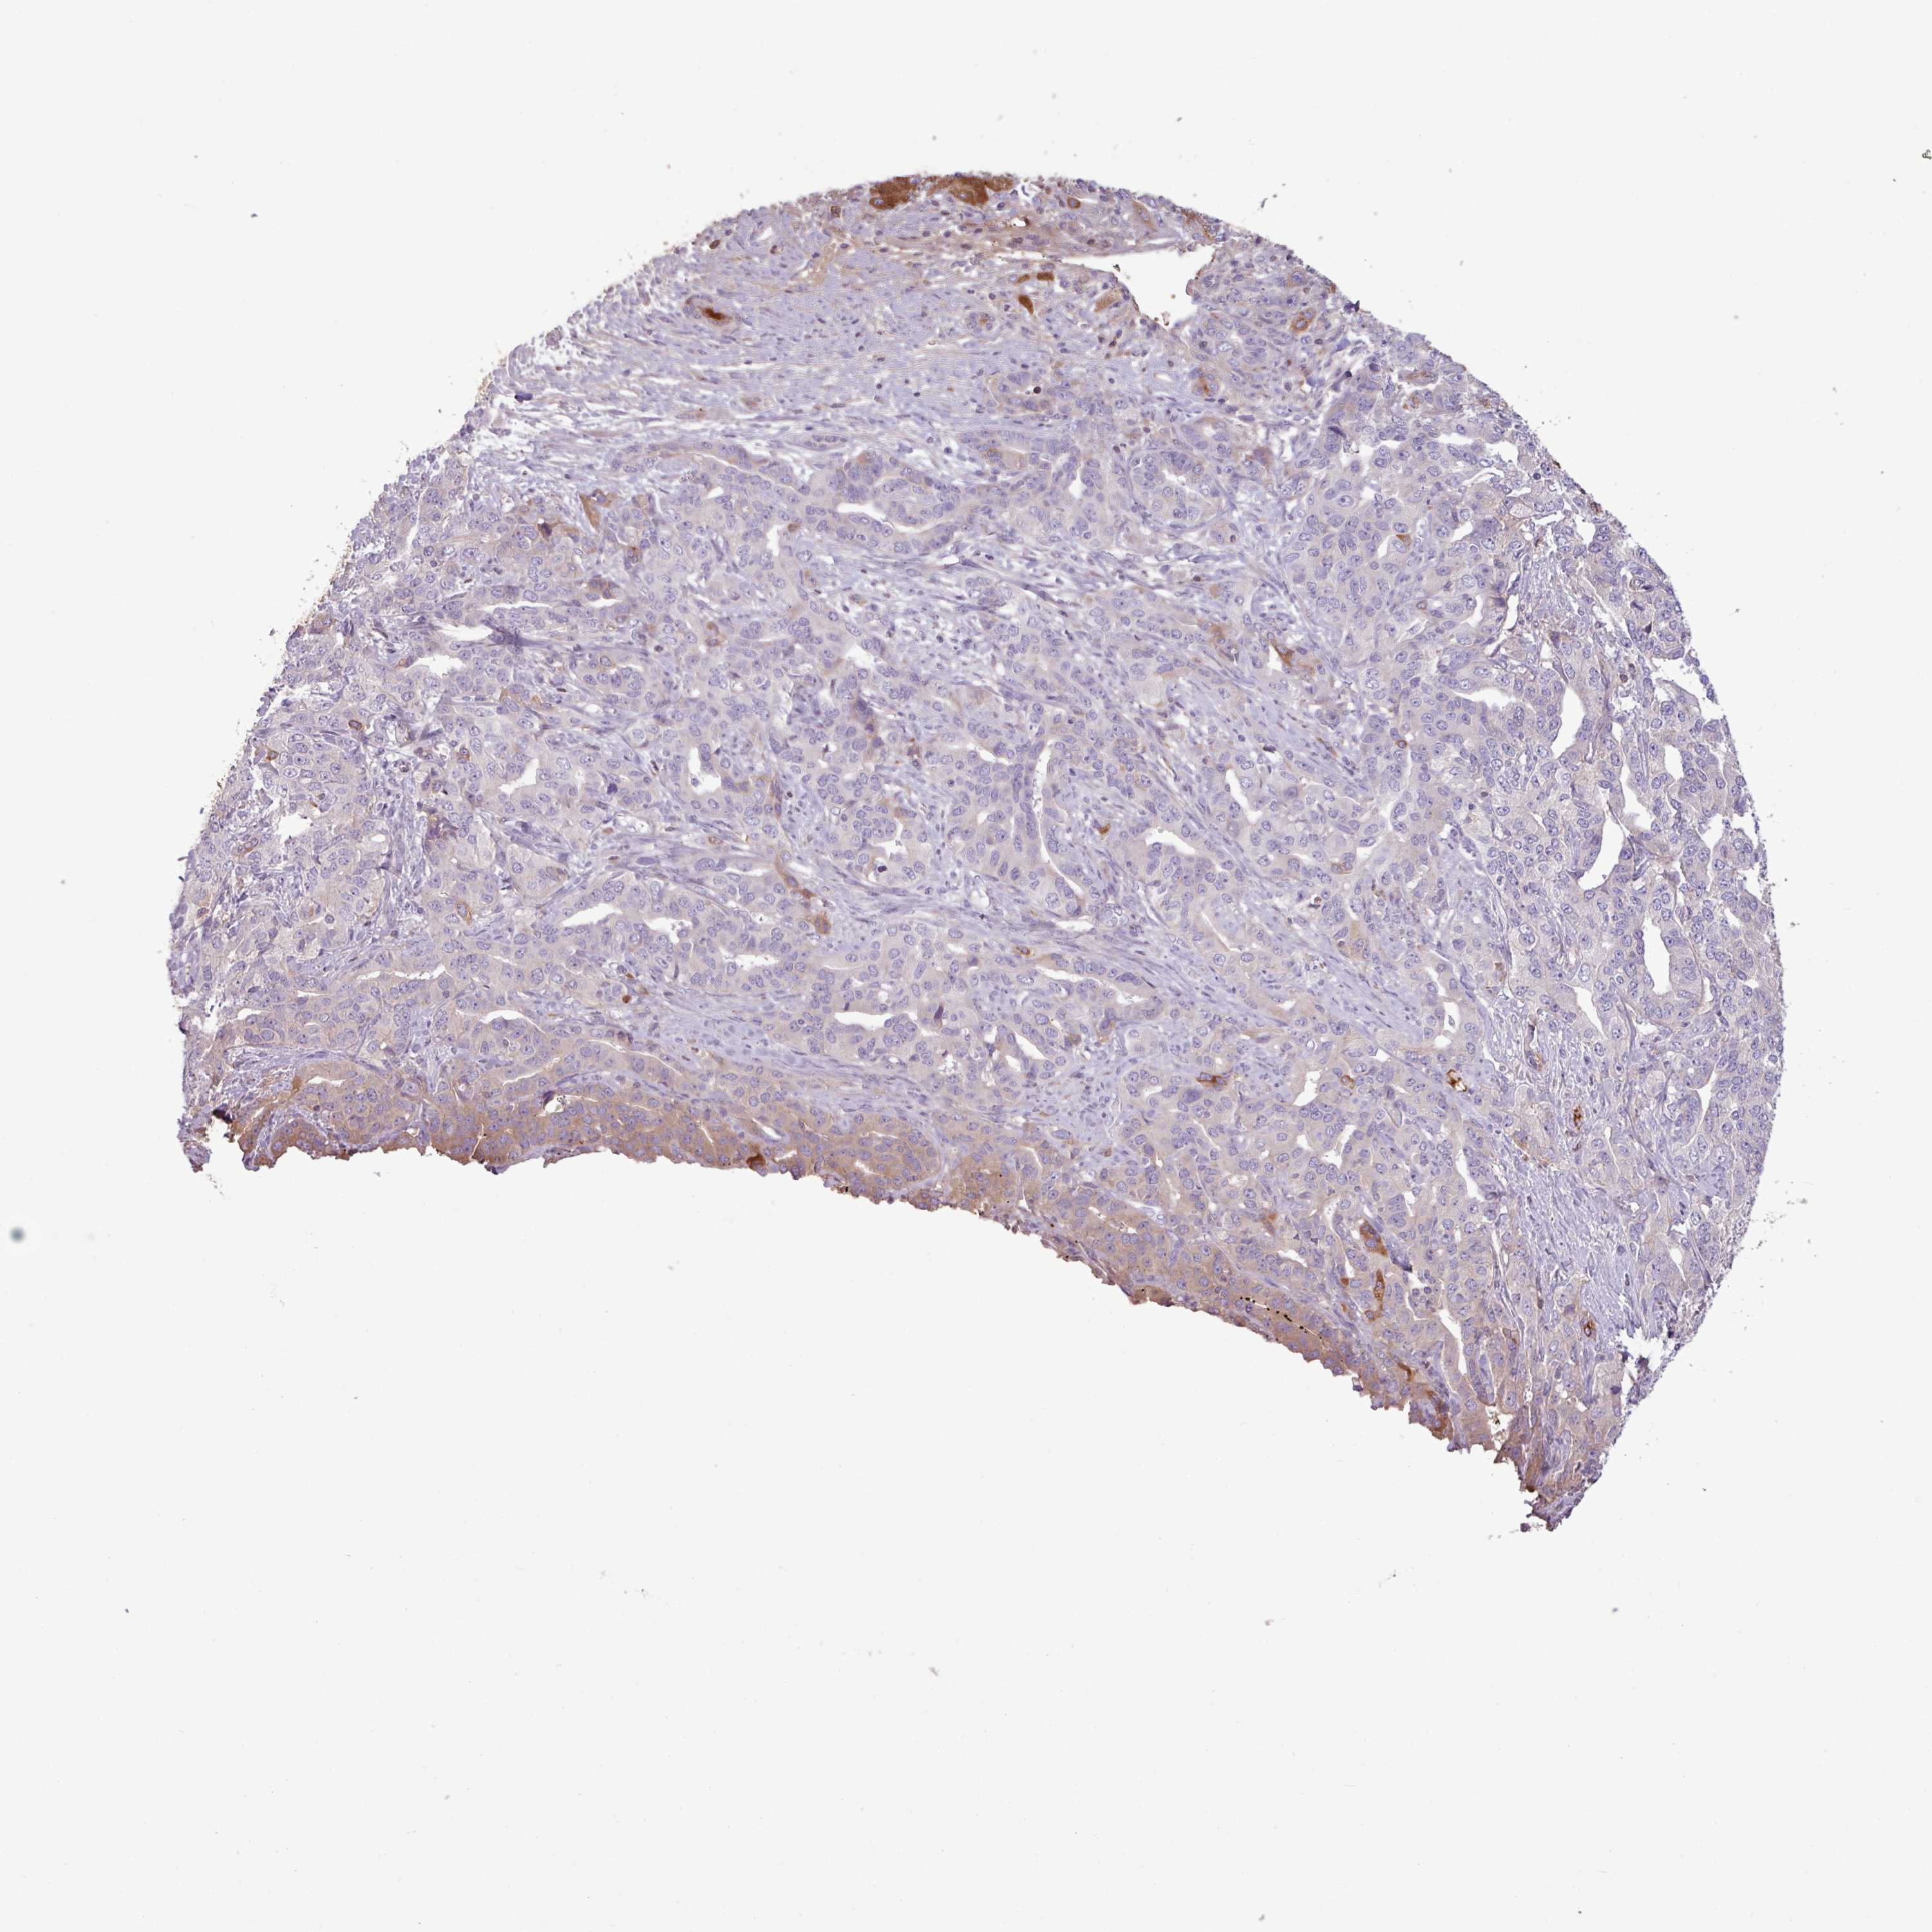

LIVER CANCER - Protein expressioni

A mouse-over function shows sample information and annotation data. Click on an image to view it in a full screen mode. Samples can be filtered based on level of antibody staining by selecting one or several of the following categories: high, medium, low and not detected. The assay and annotation is described here.

Note that samples used for immunohistochemistry by the Human Protein Atlas do not correspond to samples in the TCGA dataset.

Antibody stainingi

Antibody staining in the annotated cell types in the current human tissue is reported as not detected, low, medium, or high, based on conventional immunohistochemistry profiling in selected tissues. This score is based on the combination of the staining intensity and fraction of stained cells.

Each image is clickable and will lead to virtual microscopy that enables deeper exploration of all samples and also displays staining intensity scores, fraction scores and subcellular localization as well as patient and tissue information for each sample.

HPA046356

HPA048287

HPA050103

CAB009811

CAB032603

Staining

High

Medium

Low

Not detected

Intensity

Strong

Moderate

Weak

Negative

Quantity

>75%

75%-25%

<25%

None

Location

Nuclear

Cytoplasmic/membranous

Cytoplasmic/membranous,nuclear

Cholangiocarcinoma

Carcinoma, Hepatocellular, NOS